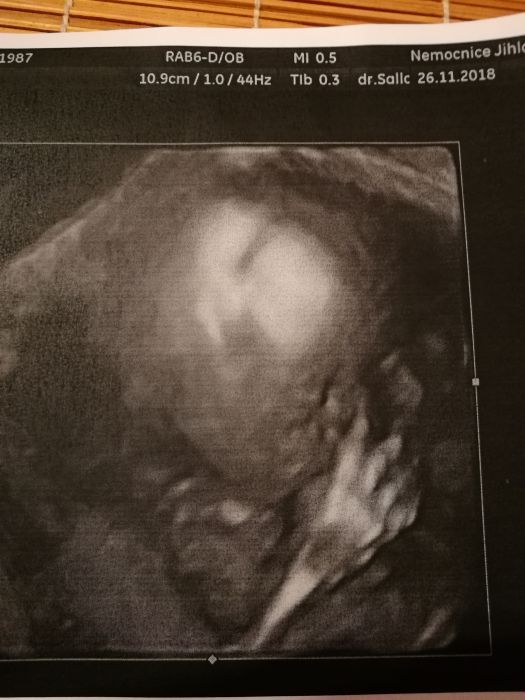

Autor: Erika87 27.11.2018 v 05:27

Holky dekuju, mne 3d delali uz na prvnim screeningu, chodim na nej do nemocnice, tam mi daji obrazek automaticky, jeste pujdeme v tom 30tt. Tohle je z toho prvniho screeningu